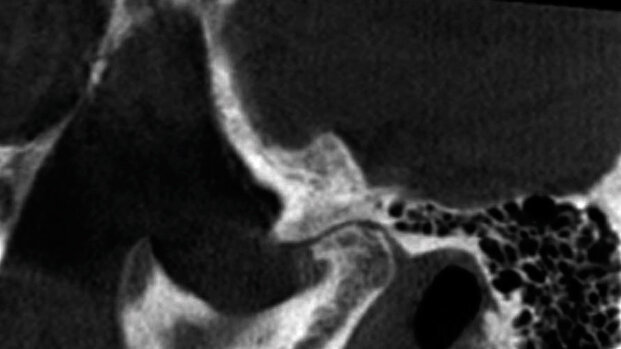

La Cone Beam Computed Tomography (CBCT) sta giocando un ruolo sempre più importante nella diagnosi e nella progettazione del trattamento implantare, e può servire come eccellente strumento preoperatorio prima di procedere al rimodellamento del seno. Quando posizioniamo gli impianti nel mascellare, dobbiamo prendere in considerazione la patologia e l’anatomia dei seni mascellari. Gli studi dimostrano che la prevalenza della patologia mucosa, secondaria a problemi endodontici e parodontali, va dal 5 al 38%. La prevalenza di patologia sinusale trovata con la CBCT in pazienti asintomatici è stata stimata tra il 25 e il 56%. La letteratura concorda sul fatto che un ispessimento della mucosa di circa 1-2 mm è normale.

Mucosite, la patologia più comune del seno, è il termine che indica ispessimento della mucosa e si associa comunemente all’infezione apicale e alle allergie. La secrezione mucosa drena dal seno attraverso l’ostio, che si trova nella parte superiore, e dovrebbe essere distante dalla zona dell’innesto chirurgico; lo svantaggio è che non c’è drenaggio gravitazionale dovuto alla posizione alta dell’ostio. L’altra patologia più comune è la cisti da ritenzione mucosa. Normalmente appare a forma di cupola e di solito è il risultato di un blocco a livello del dotto delle ghiandole mucose. I polipi del seno si formano quando c’è infiammazione e edema nella lamina propria della membrana sinusale. I polipi sono solidi, a differenza delle cisti da ritenzione, che sono ripiene di liquido. Entrambi appaiono radiograficamente simili, sebbene risulti più probabile che i polipi siano peduncolati e che la cisti abbia un’ampia base. Nelle patologie sinusali meno comuni rientra il mucocele, che si forma quando l’ostio è bloccato e il muco si accumula nel seno. I mucoceli tendono a gonfiarsi fino a causare lo spostamento della parete del seno. Quando questo si verifica, è più facile distinguere tra una grande cisti da ritenzione mucosa e un mucocele. Tumori benigni e maligni possono crescere a dismisura e sono in grado di distruggere tutti i margini del seno. Le opacità nel seno possono essere antroliti, osteomi e esostosi. Gli antroliti sono opacità derivanti dalla mineralizzazione intorno a materiale organico e non aderiscono alla parete ossea, mentre gli osteomi e le esostosi sono attaccati alla parete ossea. Infine, qualche patologia può nascere dall’esterno e invadere il seno. Esempi del genere sarebbero le cisti odontogene e le cisti radicolari. Con le modalità di CBCT imaging, la maggior parte delle patologie del seno hanno una opacità simile, il che rende difficile distinguere tra le varie patologie; si dovrebbe porre maggiore attenzione nel valutare la forma e la distribuzione delle lesioni. È quindi fondamentale avere una scansione dell’intero seno fino al piano orbitale, perché è la parte superiore della lesione che consente la definitiva diagnosi differenziale (ad esempio a forma di cupola, dritta o curvilinea). Una scansione completa dei seni aiuta anche a stabilire se l’ostio è bloccato. Un ostio bloccato avrà una maggiore probabilità di morbilità conseguente a chirurgia implantare poiché non sarà in grado di drenare adeguatamente batteri e detriti. Va fatto notare che devono essere rinviati tutti i pazienti con segni di patologia sinusale, che debbano fare o no innesto osseo o impianti.